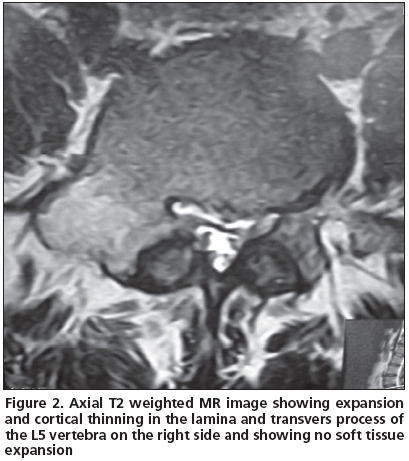

A 21 year-old male patient admitted to our clinic with low back pain persistent to medication for the last 3 years. He was first referred to physical medicine and rehabilitation department and then to a neurosurgery department after several visits because of persistent pain. He had no history of trauma. His pain was not aggravated by coughing, standing or sitting; and the pain was not relieved by salicylates or NSAIDs. Whole blood count (CBC), erythrocyte sedimentation rate (ESR) and rheumatoid factor (RF) were found within normal limits. Physical examinations were found normal except the tenderness extending from T12 to L5 associated with paravertebral muscle spasm. His lumbosacral CT was taken and then a tumoral mass was noticed enlarging transverse process and right lamina of L5 vertebrae with probable diagnosis of osteoblastoma or osteoid osteoma. The mass had a lytic nature with well defined osteosclerotic boundaries and facet joints were normal (Figure 1). An MRI was taken to evaluate the soft tissue expansion which showed no affection (Figure 2). A CT-guided biopsy resulted with unsatisfactory sample gathering. Then he has taken to the operation theatre and curettage and frozen section was performed since the probable diagnosis was osteoblastoma. After confirmation of benign tumoral process, the cavity was filled with allograft. The histopathological examination confirmed the diagnosis of osteoblastoma. Following surgery, the patient was asymptomatic; there was no neurological dysfunction and no residual pain or discomfort. No recurrence has been observed for four years.

Osteoblastomas are composed of an abundantly vascular connective-tissue stroma with active production of osteoid and primitive woven bone. A central lucency with a variable zone of peripheral sclerosis is the typical pattern; osteolysis and mass effect are frequently present[3]. It can be seen in any area of skeleton but it is the only benign tumor which shows primary affection to spinal column, and both the body and posterior arch of vertebrae[3,5]. The diagnostic radiographic feature is usually a single, round area of osteolysis which expands the bone and it is not always with well defined boundaries. Marked osteolysis may be seen around the lesion which is not as extensive as in osteoid osteoma[6]. Histologically, osteoid osteomas and osteoblastomas are similar. Their most remarkable difference is: osteoblastoma has an unlimited growth potential with a capability of malignant transformation and is larger in size (usually larger than 2 cm). Plain radiography and CT findings are similar, including radiolucent nidus, matrix calcifications, and accompanying bony sclerosis. Differentiation is made on the basis of size, and the larger lesions are typically categorized as osteoblastoma, but osteoblastoma detected early and not exceeding a diameter of 2 cm makes the distinction difficult. Then, clinical presentation plays an important role in the diagnosis. Osteoblastomas are known to have a high incidence of neurological deficit. Neurologic involvement has been reported in 25–50% of patients. The tumor located in the spine can cause neurological symptoms. The case presented here had no neurological deficit.